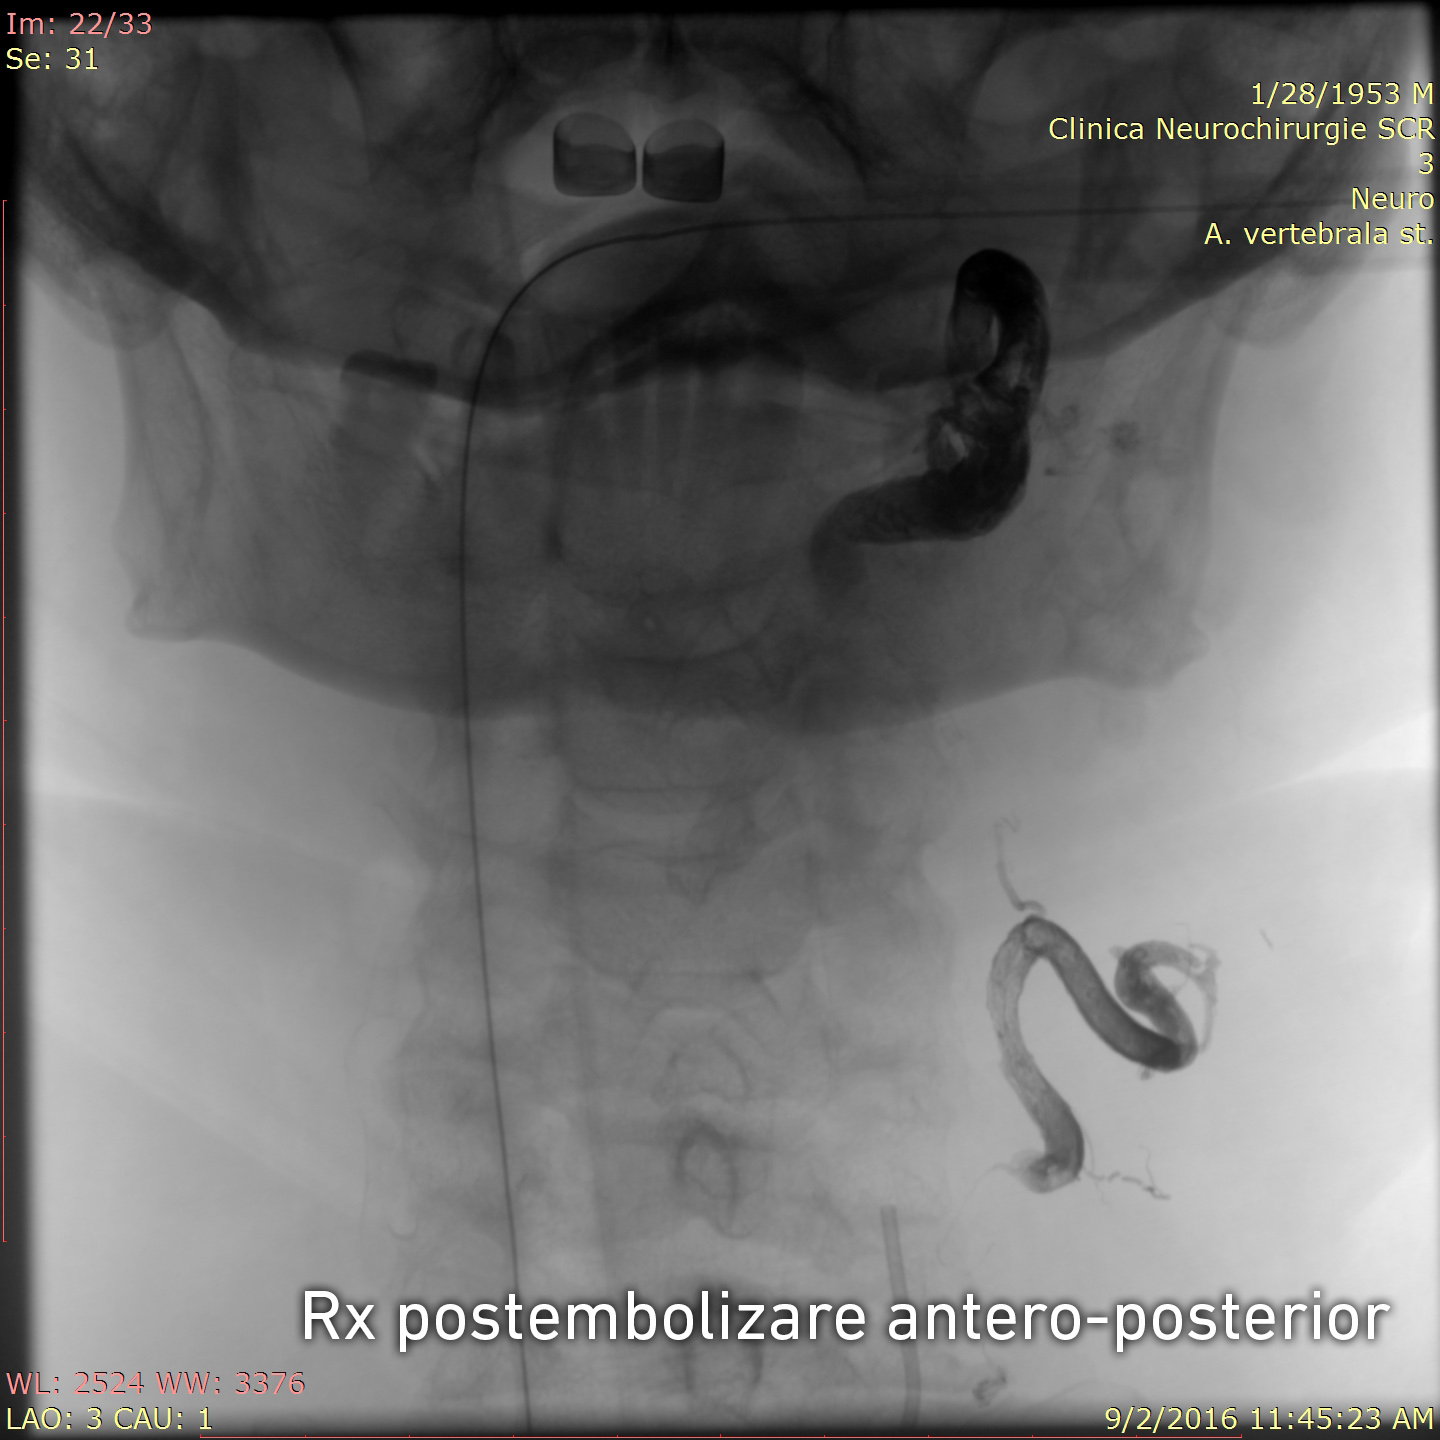

Tratamentul endovascular a fost realizat grație colaborării multidisciplinare între neurochirurgul-intervenționist Alexandru Șumleanschi, cardiologul-intervenționist Eugen Calenici și neuro-anestezisteziolog Iana Cotorcea. Embolizarea a avut loc în 2 etape sub anestezie generală : pe 15.07.2016 a fost ocluzată artera cervicală ascendentă stângă (trunchiul tireo-cervical) cu Onyx și pe 02.09.2016 a fost realizată ocluzia arterei vertebrale stângi (segmentul V2-V3). Toate obiectivele propuse înainte de operație au fost realizate cu succes. Starea pacientului s-a ameliorat după embolizare: au dispărut acufenele, au diminuat durerile nevralgice, ceea ce a permis diminuarea tratamentului neurotrop. Spre deosebire de chirurgia clasică, pacientul a necesitat timp redus de spitalizare și recuperarea după embolizare a fost rapidă.